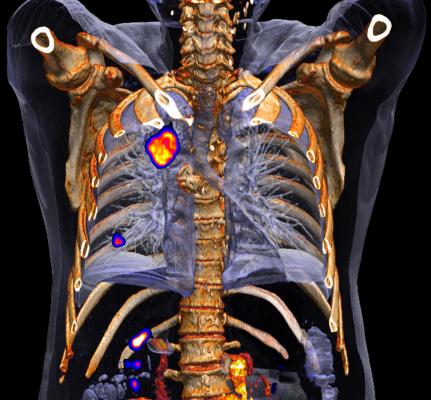

A An 81 Year Old Patient With Centrally Located Non Small Cell Lung Download Scientific Diagram